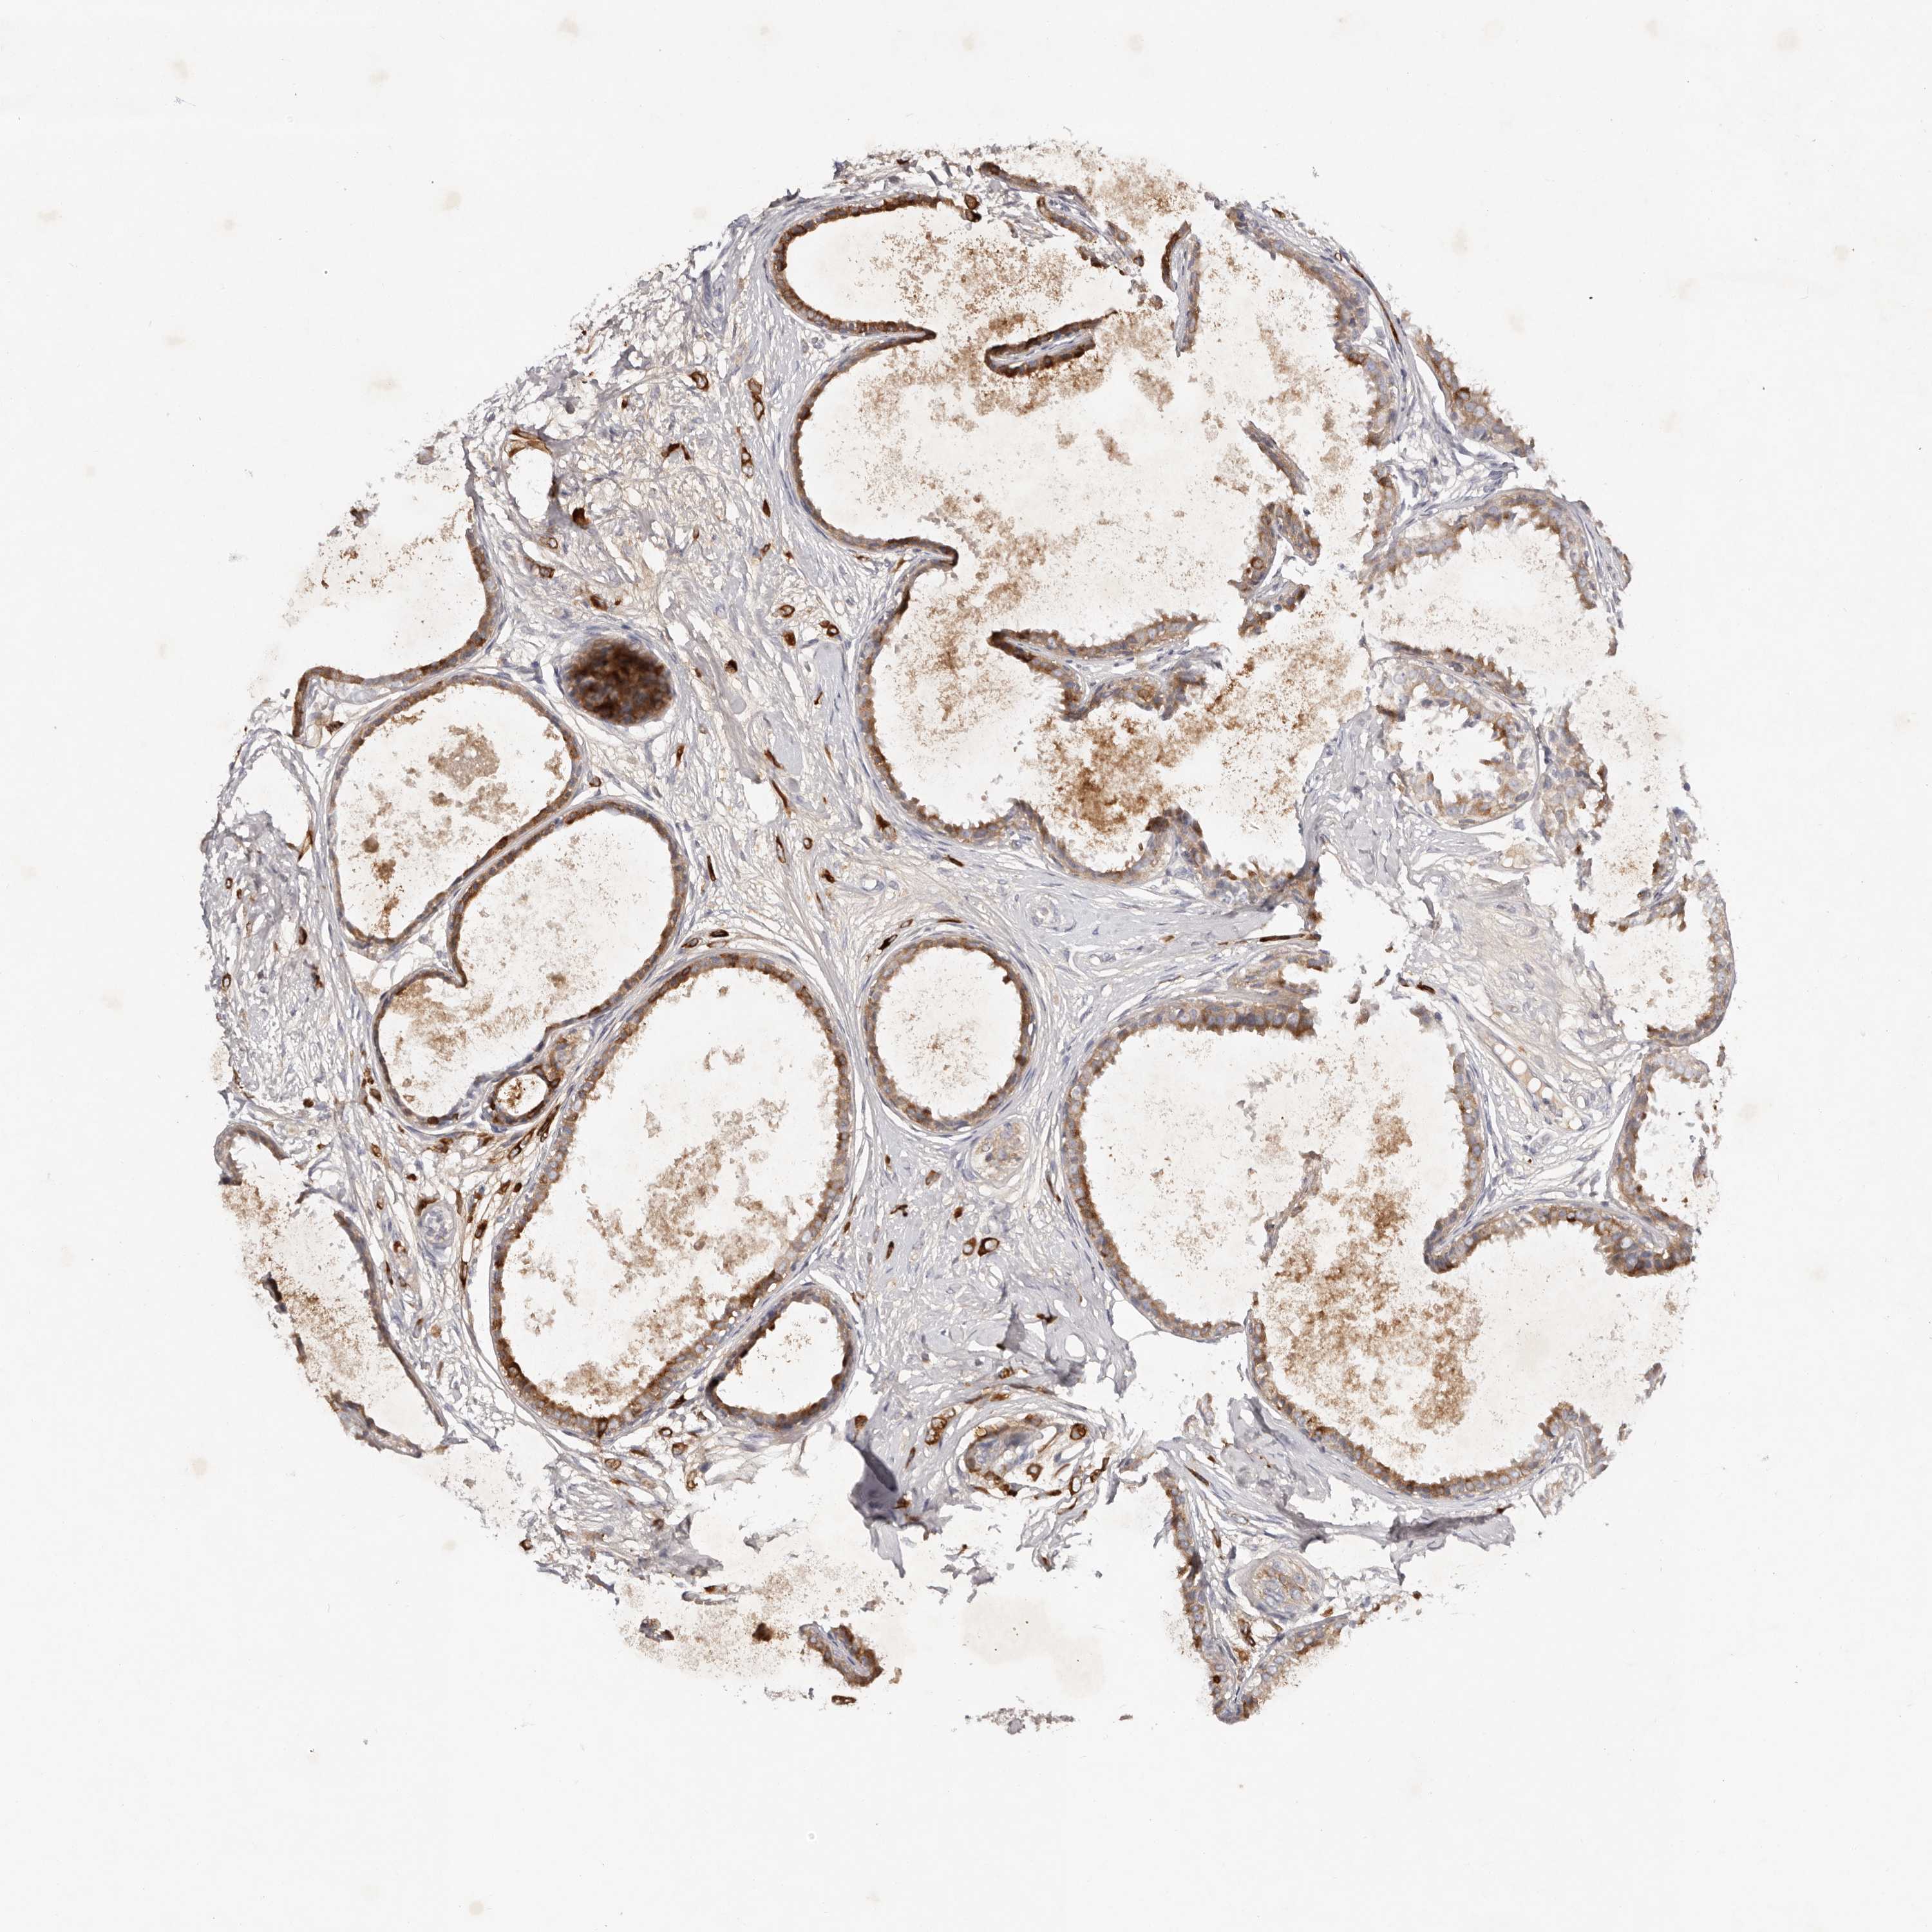

CANCER BREAST CANCER Show tissue menu

BRCA TCGA BRCA VALIDATION PROTEIN EXPRESSION